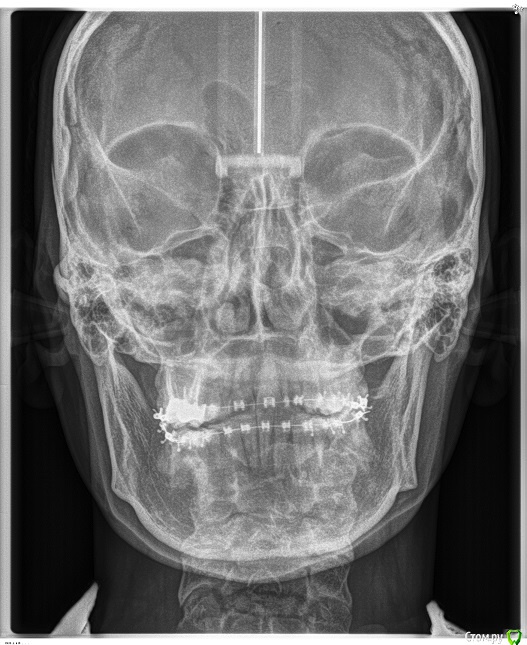

on1976 Опубликовано 18 июля, 2019 Поделиться Опубликовано 18 июля, 2019 (изменено) Добрый день!У меня огромная проблема,Я попала в чудовищную ситуацию в лечении зубов брекетами и вот это длится уже 4 года.По итогу на сегодняшний день, у меня проблемы со здоровьем, депрессия, очень изменилось лицо и прочие последствия.Случайно наткнулась на статьи о "ALF ортодонтия" и прочла об основателе ортокраниодонтии и данного метода в России Алексее Олеговиче Савинове, Skip, но найти информацию и записаться на приём я нигде не могу. А мне важно его мнение по моей ситуации. Сил моих уже больше нет лечиться поскольку улучшений нет. Помогите найти координаты и записаться на приём Савинову.Я прикрепляю файлы ренгена. Может кто выразит своё мнение. (приложенные сними на начальном этапе лечения, сейчас изменения есть, но общая картина изменилась в худшую сторону.)Ортокраниодонтия как последняя надежда! Буду благодарна если получу от вас обратную связьмой тел 89272818180e-mail: on1976@yandex.ru С уважением Сальникова Ольга. Изменено 18 июля, 2019 пользователем on1976 Ссылка на комментарий

on1976 Опубликовано 23 июля, 2019 Автор Поделиться Опубликовано 23 июля, 2019 Ортокраниодонтия - это альтернативная ортодонтия, то есть по факту - те же возможности, но другими методиками. В вашем случае прямые показания к ортогнатической хирургии. В Астрахани есть хороший ортодонт - пишите в личкуТак -то оно так, но в течении 4 лет ношения брекетов, положение стало меняться, и я задумалась о возможности решения альтернативным способом, перекос верхней части стал меньше. Возможно это можно решить ALF капой? Ссылка на комментарий